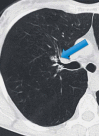

Endoscopic lung volume reduction (ELVR) is being adopted as a treatment option for carefully selected patients suffering from severe emphysema. ELVR with the one-way endobronchial Zephyr valves (EBV) has been demonstrated to improve pulmonary function, exercise capacity, and quality of life in patients with both heterogeneous and homogenous emphysema without collateral ventilation. In this "expert best practices" review, we will highlight the practical aspects of this therapy. Key selection criteria for ELVR are hyperinflation with a residual volume >175% of predicted, forced expiratory volume <50% of predicted, and a 6-min walking distance >100 m. Patients with repeated infectious complications, severe bronchiectasis, and those with unstable cardiovascular comorbidities should be excluded from EBV treatment. The procedure may be performed with either conscious sedation or general anesthesia and positive pressure mechanical ventilation using a flexible endotracheal tube or a rigid bronchoscope. Chartis and EBV placement should be performed in 1 procedure when possible. The sequence of valve placement should be orchestrated to avoid obstruction and delivery of subsequent valves. If atelectasis has not occurred by 1 month after procedure, evaluate valve position on CT and consider replacing the valves that are not optimally positioned. Pneumothorax is a common complication and typically occurs in the first 2 days following treatment. A management algorithm for pneumothorax has been previously published. Long-term sequelae from EBV therapy do occur but are easily manageable.